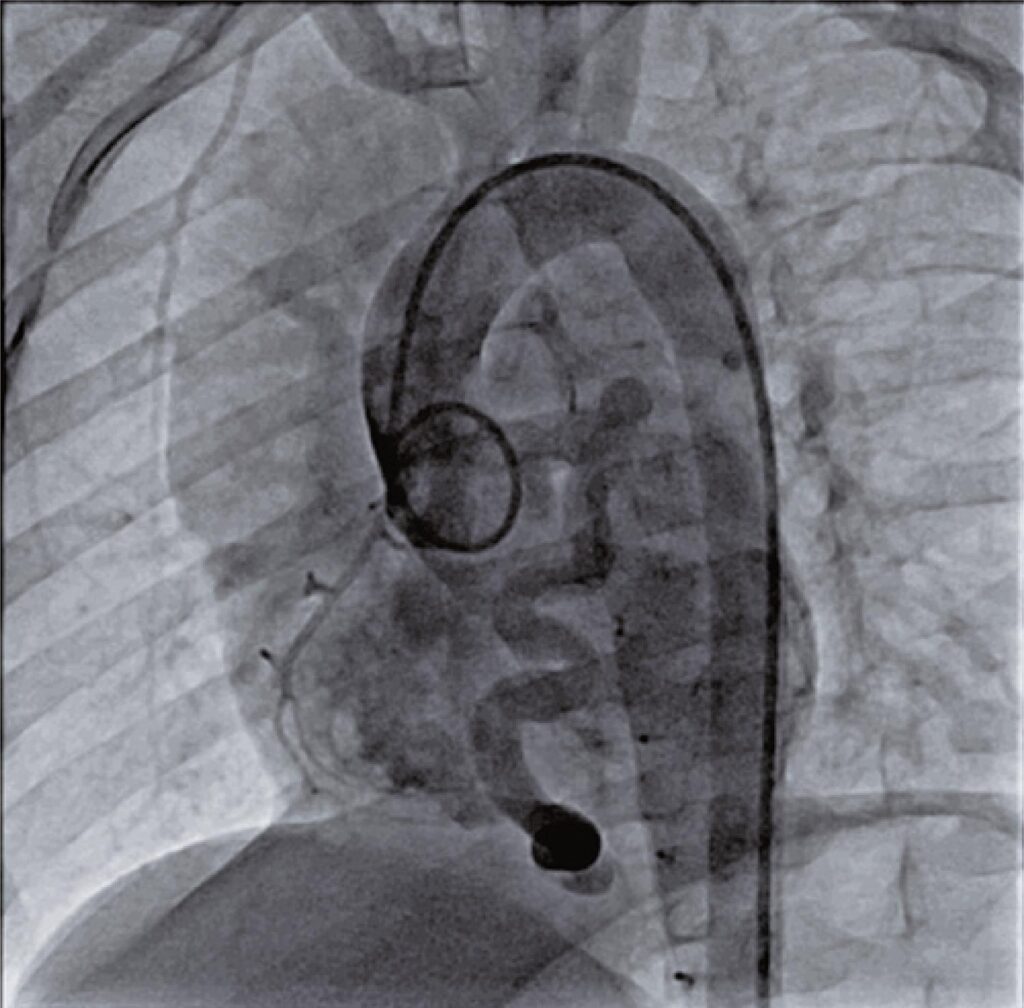

As fístulas das artérias coronárias são anomalias congênitas raras e caracterizam uma comunicação anormal entre as artérias coronárias e as câmaras cardíacas ou grandes vasos. Muitos dispositivos que incluem vários coils, plugues vasculares, oclusores e stents recobertos têm sido usados no fechamento transcateter de fístulas de artérias coronárias. Neste relato, realizamos com sucesso o fechamento de uma fístula de artéria coronária, entre a artéria descendente anterior e o ápice do ventrículo direito, usando o dispositivo Amplatzer Piccolo™, anteriormente chamado de tamanho adicional do Amplatzer™ Duct Occluder. Em nossa opinião, o dispositivo Amplatzer Piccolo™ é adequado para oclusão transcateter de fístula da artéria coronária, podendo ser usado no lugar de plugues vasculares.